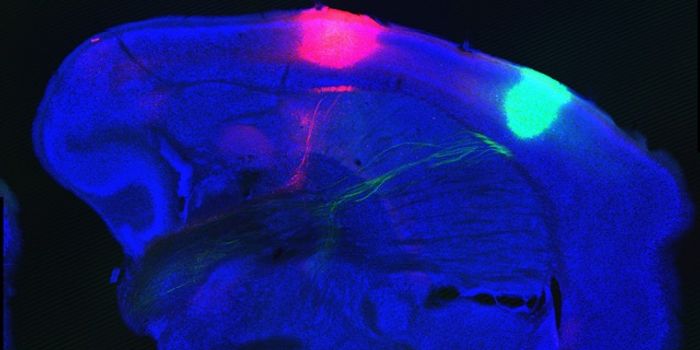

MAR 16, 2016NeuroscienceChemogenetics and especially optogenetics have been game-changers in neuroscience research. By providing precise control ...